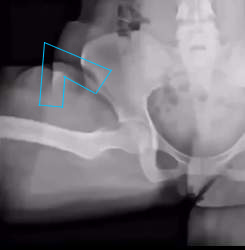

>最初の奴アウトかどうかだけ教えて欲しい

曲がっている太ももの付け根の上あたりによくわからない深い亀裂が入っている

これはかなりまずい状態だと思う

>曲がっている太ももの付け根の上あたりによくわからない深い亀裂が入っている

>これはかなりまずい状態だと思う

ここの骨は元々こうだよ!

亀裂じゃなくて服のシワでは?

動画再生前のサムネイル状態では太ももを水平にした状態になっていると思うんだけど

画像の上の文字「画像ファイル名:」のイの位置からまっすぐ下に向かって見ると太ももの肉を縦に切り裂いたような断裂がある

服や骨格のようには見えないと思う

それはただのシワだろう

シワというかこの写真の人脚太いから肉が別れたように見えてんのよ

>それはただのシワだろう

普通こんな断裂映るわけがない

>普通こんな断裂映るわけがない

多分否定してる「」は答えられないから俺が答えるが大腿骨頭にくっついてる大腿骨頭靭帯じゃろう

fu6179744.jpg

>fu6179727.jpg

左は成長期の股関節じゃないか

左のは骨端線で骨折ではない